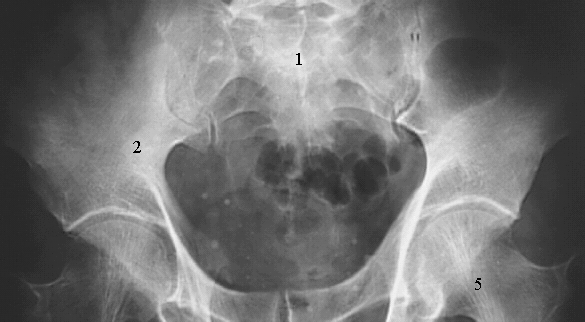

Pelvis & Perineum: Pelvic Radiograph

1. Sacrum

2. Iliac Fossa

5. Femoral Neck